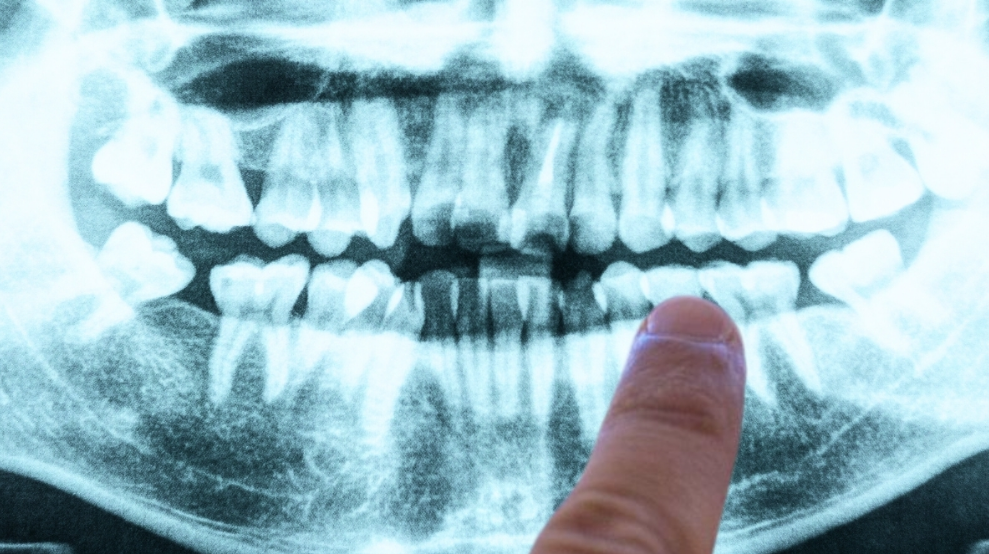

Một nghiên cứu đã gợi mở manh mối được coi là rõ ràng nhất về tác nhân vi khuẩn có thể đứng sau bệnh Alzheimer, và nó xuất phát từ một nguồn ít ai ngờ tới: bệnh viêm lợi. Ảnh: Canva

Các nghiên cứu mới liên tục chỉ ra rằng quá trình hình thành Alzheimer phức tạp hơn rất nhiều so với quan niệm truyền thống. Một trong những công trình gây chú ý nhất mới được công bố trên tạp chí Science Advances cho thấy, viêm lợi mãn tính có thể liên quan chặt chẽ tới cơ chế bệnh sinh của Alzheimer.